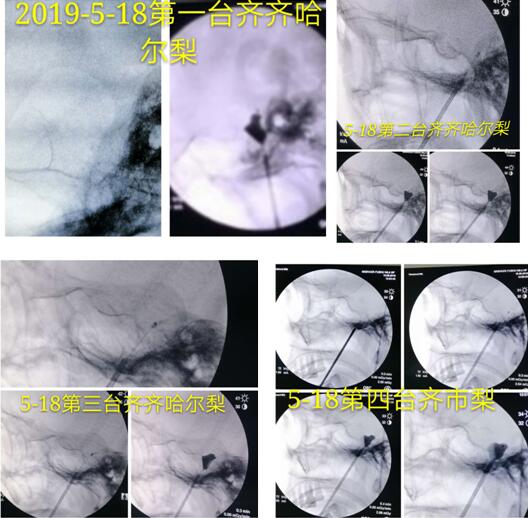

当日上午,马逸教授在我院门诊综合楼一楼大厅开展了义诊活动,他耐心细致地为前来咨询的患者答疑解惑。随后,在完善的医疗设施和精心的术前准备下,马逸教授为4位饱受三叉神经痛折磨的患者完成手术,手术一气呵成、十分顺利,现场观摩专家惊叹不已。

4例手术影像资料